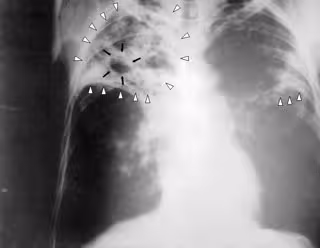

tuberculosis